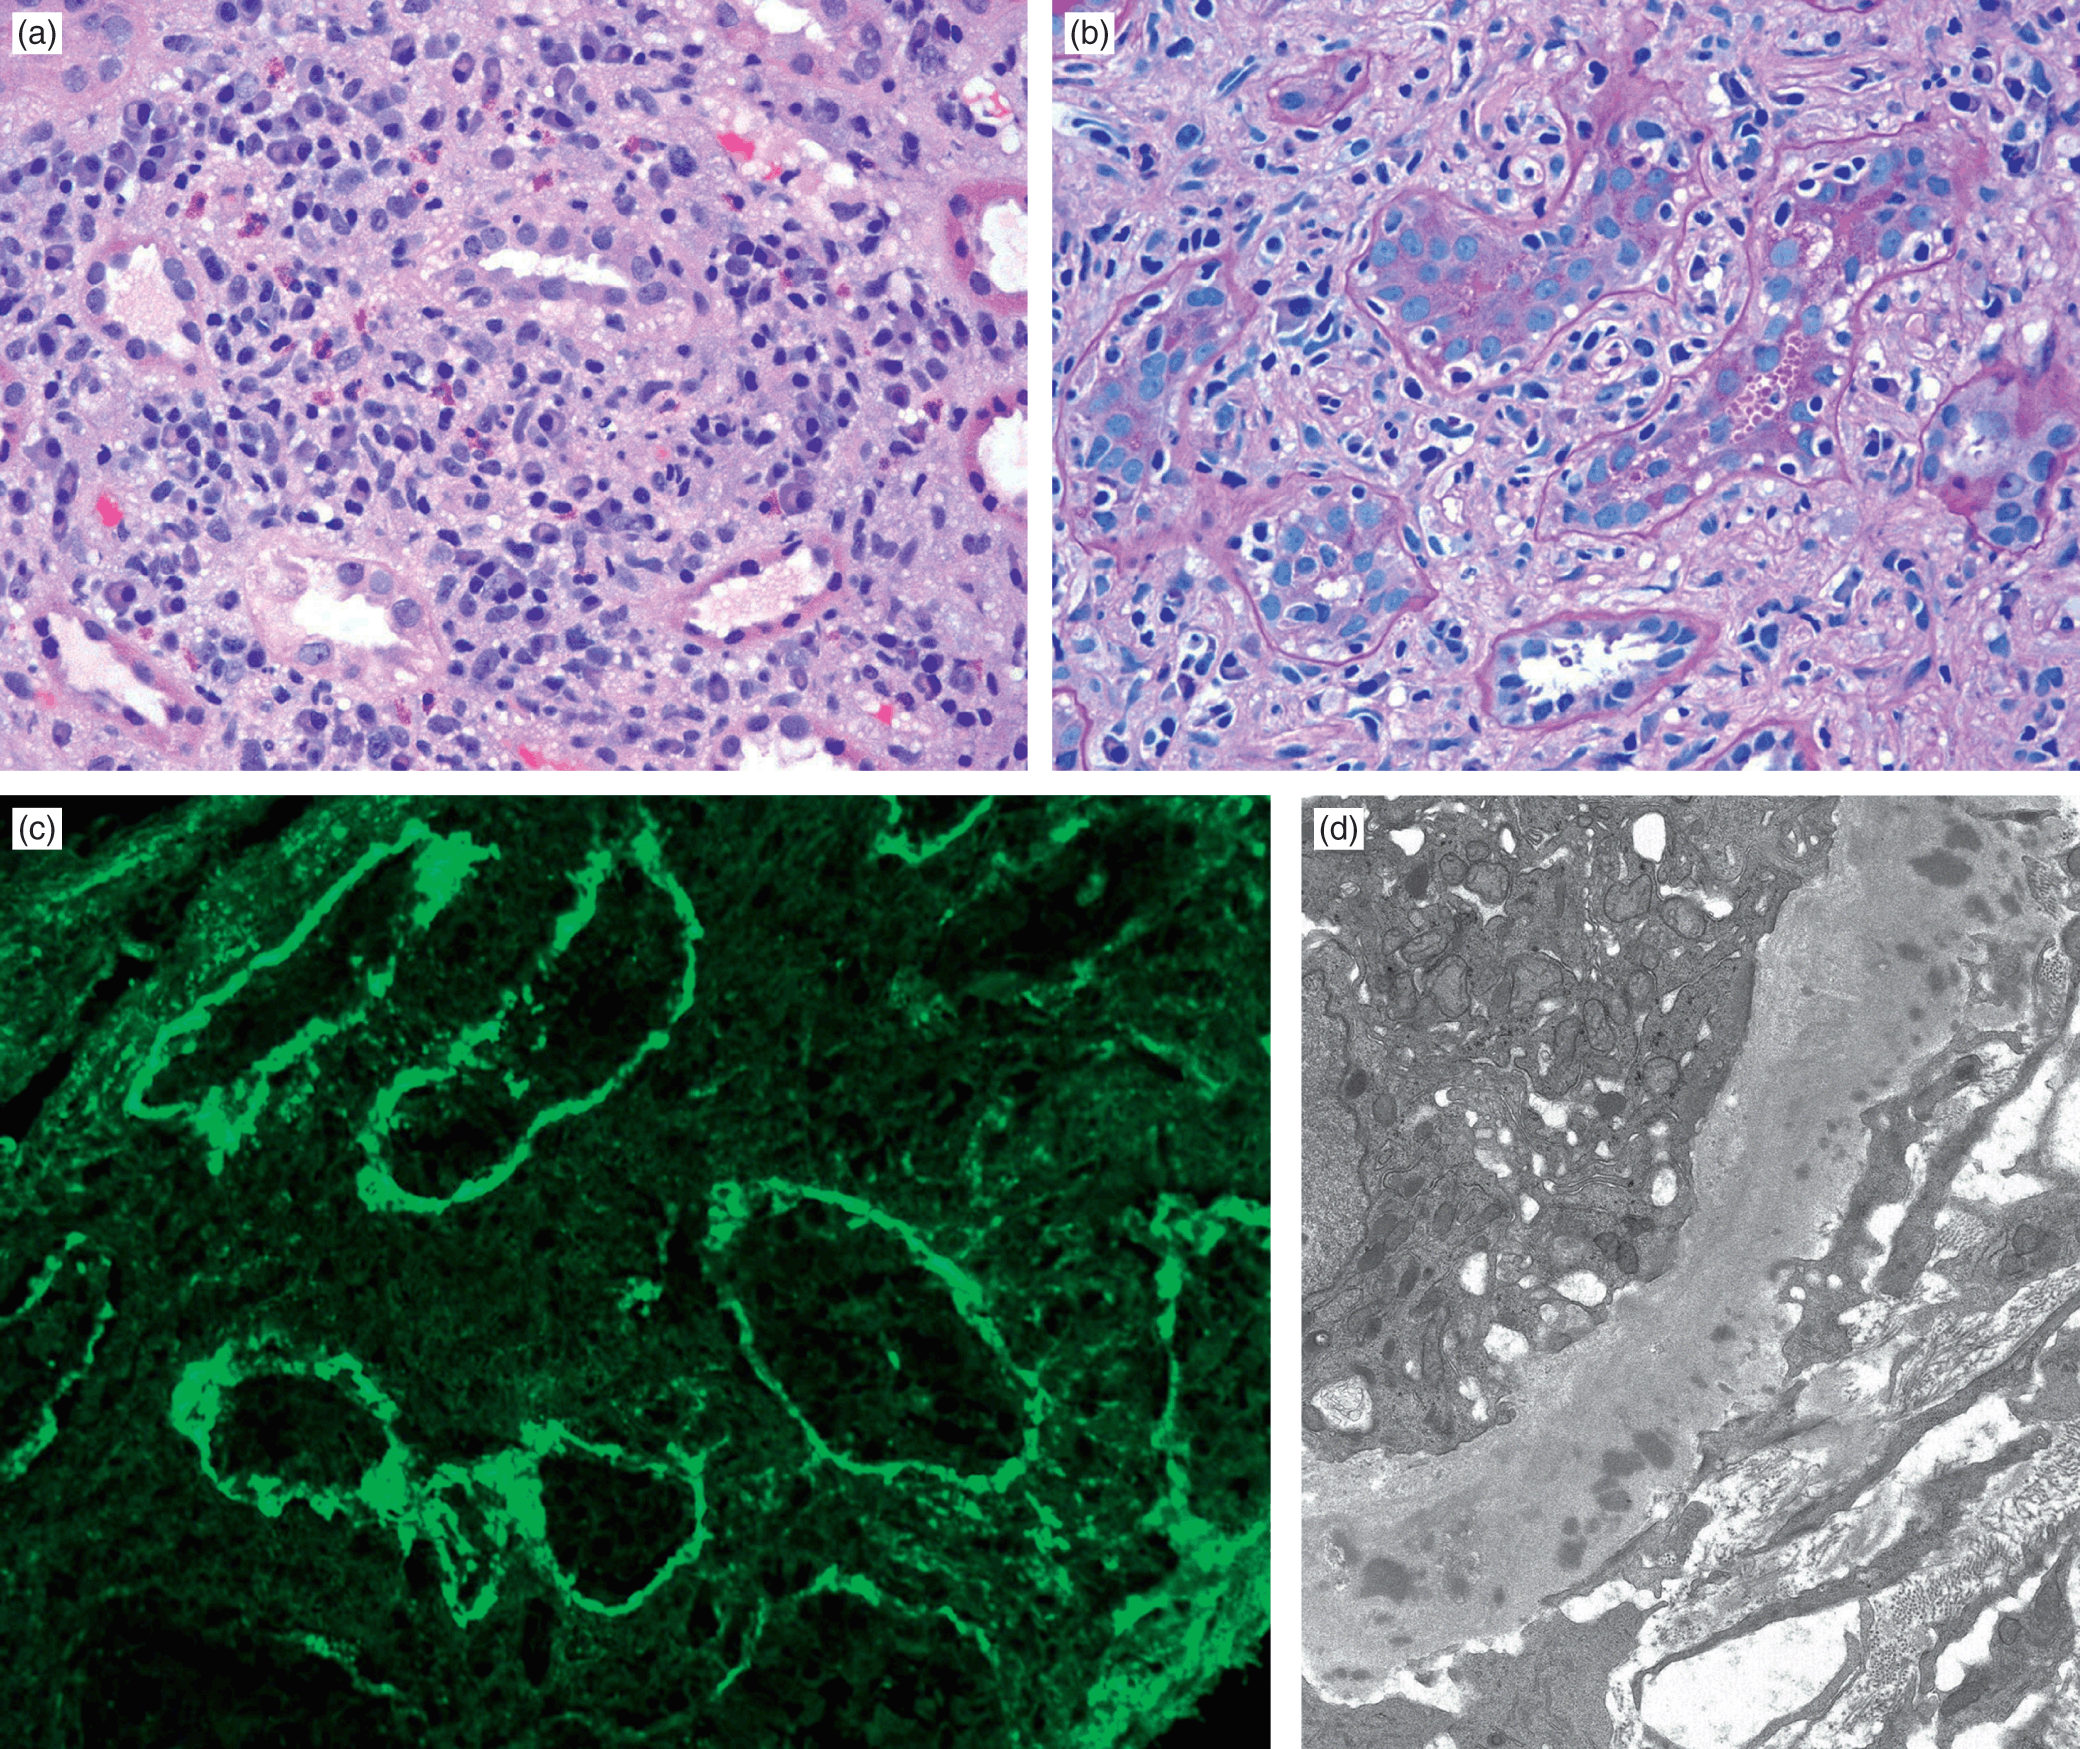

9b70fea5-1079-4abc-a0df-, Heptinstall's Pathology of the Kidney: 9781451144116,

Heptinstall's Pathology of the Kidney: 9781451144116, Heptinstall's Pathology of the Kidney: 9781451144116,

Heptinstall's Pathology of the Kidney: 9781451144116, Heptinstall's Pathology of the Kidney: 9781451144116,

Heptinstall's Pathology of the Kidney: 9781451144116, Renal Pathology of Ciliopathies - Thivya Sekar, Neil J,

Renal Pathology of Ciliopathies - Thivya Sekar, Neil J, Renal Pathology of Ciliopathies - Thivya Sekar, Neil J,

Renal Pathology of Ciliopathies - Thivya Sekar, Neil J, Heptinstall's Pathology of the Kidney: 9781975161538,

Heptinstall's Pathology of the Kidney: 9781975161538, Non-neoplastic renal diseases (Chapter 31) - Silverberg's,

Non-neoplastic renal diseases (Chapter 31) - Silverberg's, The Aging Kidney and End-stage Renal Disease (Chapter 15,

The Aging Kidney and End-stage Renal Disease (Chapter 15, Renal Pathology of Ciliopathies - Thivya Sekar, Neil J,

Renal Pathology of Ciliopathies - Thivya Sekar, Neil J, Practical Approach to Congenital Anomalies of the Kidneys,

Practical Approach to Congenital Anomalies of the Kidneys, Cystic Diseases and Developmental Kidney Defects | Abdominal Key,

Cystic Diseases and Developmental Kidney Defects | Abdominal Key, The Aging Kidney and End-stage Renal Disease (Chapter 15,

The Aging Kidney and End-stage Renal Disease (Chapter 15, Tubulointerstitial Diseases (Chapter 12) - Silva's,

Tubulointerstitial Diseases (Chapter 12) - Silva's, Diagnostic Pathology: Kidney Diseases: 9780443107177

Diagnostic Pathology: Kidney Diseases: 9780443107177